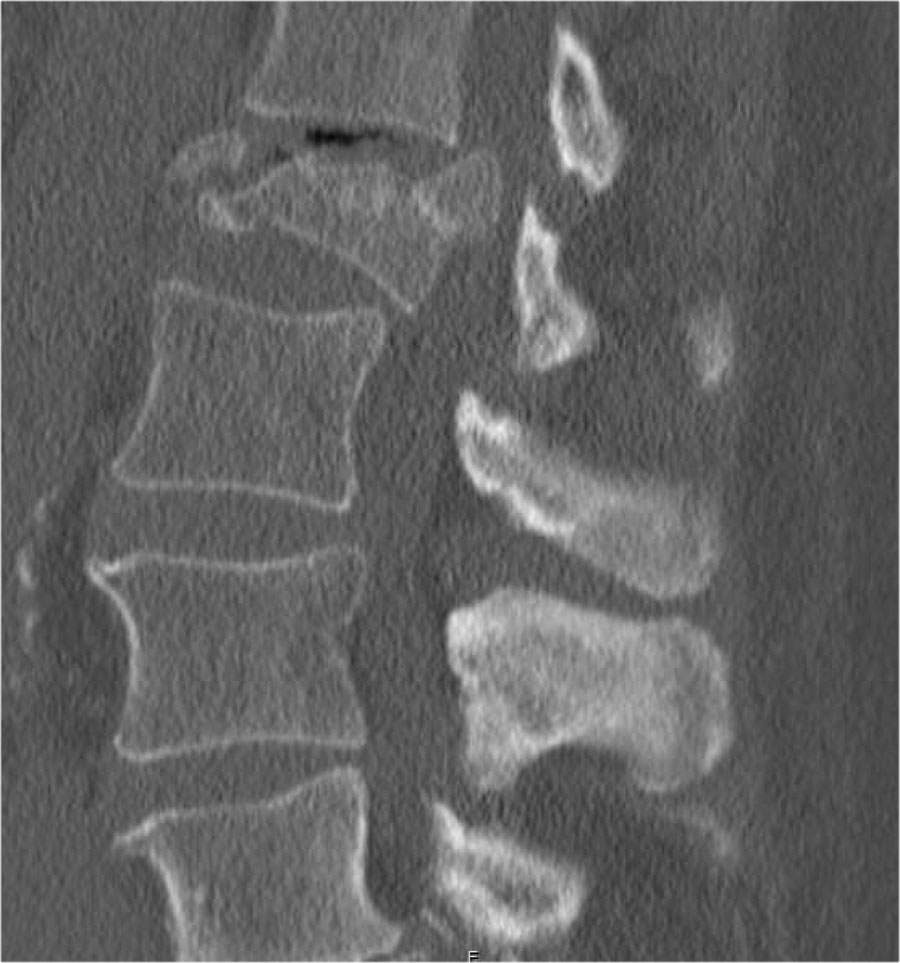

Mảnh xương góc sau trên thân đốt sống bị đẩy lùi ra sau (Retropulsion)

Hiện tượng mảnh xương bị đẩy lùi ra sau là đặc điểm điển hình của gãy vỡ, phân biệt rõ ràng với gãy nén đơn thuần.

Cuộn qua các hình ảnh.

Gãy theo mặt phẳng đứng dọc của thân đốt sống và

cung sau đốt sống

Gãy theo mặt phẳng đứng dọc của thân đốt sống và gãy cung sau theo mặt phẳng đứng dọc gặp lần lượt trong 90% và 85% các trường hợp gãy vỡ.

Dưới đây là bốn ví dụ minh họa.

Trong phân loại Denis, đây sẽ là gãy ba cột — trước/giữa/sau — cho thấy gãy xương rất không vững.

Tuy nhiên, trong phân loại TLICS, đây là gãy vỡ, tức là 2 điểm cho hình thái.

Phương pháp điều trị sẽ phụ thuộc vào tính toàn vẹn của PLC và tình trạng thần kinh.